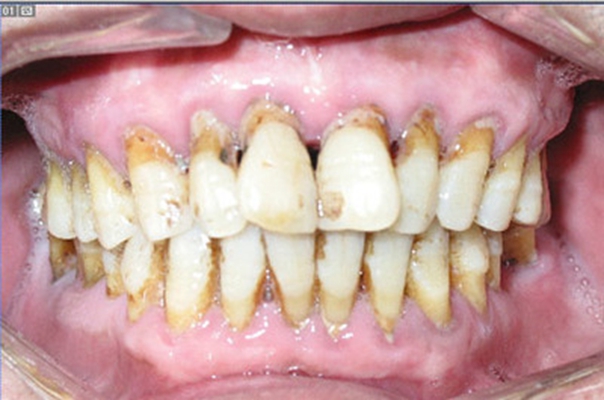

牙周炎圖片

牙周袋 (7)